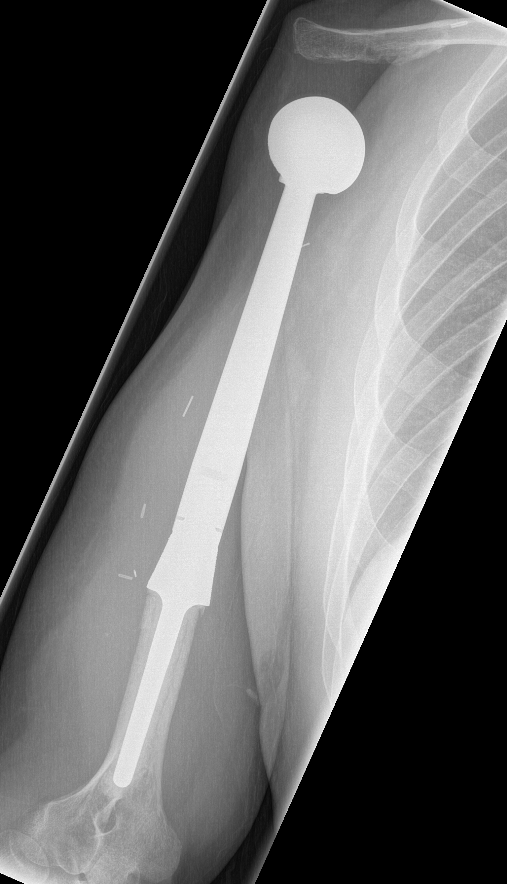

Large calcification with endosteal scalloping humerus

Large calcified lesion with endosteal scalloping